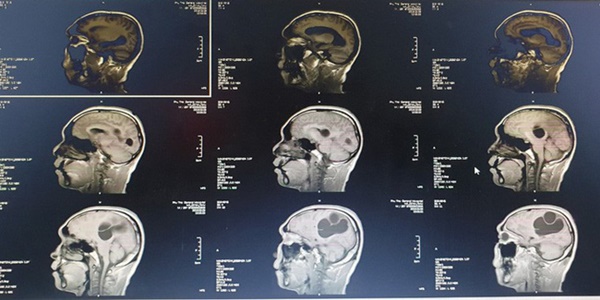

Phim chụp cho trường hợp bệnh nhân N.

Tại bệnh viện Đa khoa tỉnh Phú Thọ, người bệnh được chỉ định chụp CT sọ não, kết quả cho thấy ổ sán não khổng lồ ở bán cầu trái và vùng thái dương đỉnh phải. Phù não đè đẩy đường giữa. Bệnh nhân được chỉ định can thiệp ngoại khoa cấp cứu vào lúc 23 giờ ngày 09/03.